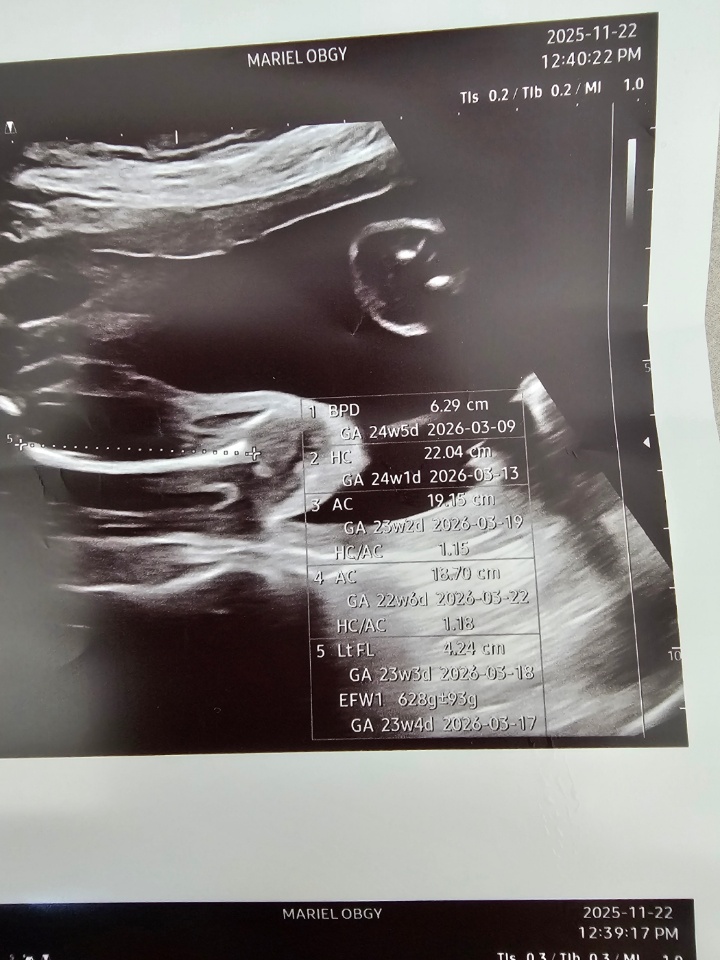

임신25주차2일인데

애기 크기가 2주작대요..그전까지는 계속 정상이었는데ㅠㅠ..잘크게 하는법이나 비법이 있을까요?경부도 파여있어서 조산위험 있다그러고 하위태반도있고..너무 걱정많은 하루에요 태동은 너무 잘 느끼고 있는데 괜찮은거겠죠?